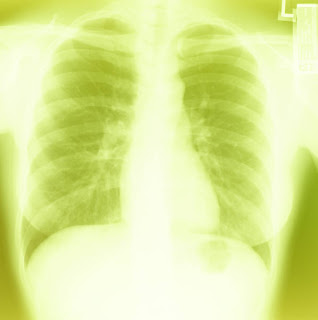

Arabie Saoudite : La Radiographie du Thorax

En 2002, si vous aviez demandé un étudiant de troisième année des études médicales quelles étaient les meilleures conditions pour effectuer une radiographie du thorax, il vous aurait dit que l'une des conditions était de l'exécuter avec le patient torse nu. Dans mon pays, les techniciens demandent toujours aux patients d'enlever leurs vêtements avant de procéder avec l'examen parce qu'ils avaient été formés que les vêtements pouvaient interférer avec les rayons X.

Dans les rares hôpitaux que j'ai visitée, j'ai remarquée que le plus souvent les femmes gardent leurs vêtements pendant l'examen. Apparement, cela ne semblait pas gener qu'elles soient trop habillées. J'ai vu un seul cas où le technicien avait demandé la patiente de se déshabiller et de porter une blouse de malade avant l'examen. La garde malade était restée derrière les rideaux pour aider son patient à porter la blouse. Je n'ai jamais cessé de me demander si la radiographie pulmonaire fait dans les cas où les patients étaient habillés étaient de très bonne qualité. Si ce n'était pas le cas est-ce que l'on fera quelque chose à ce sujet ?